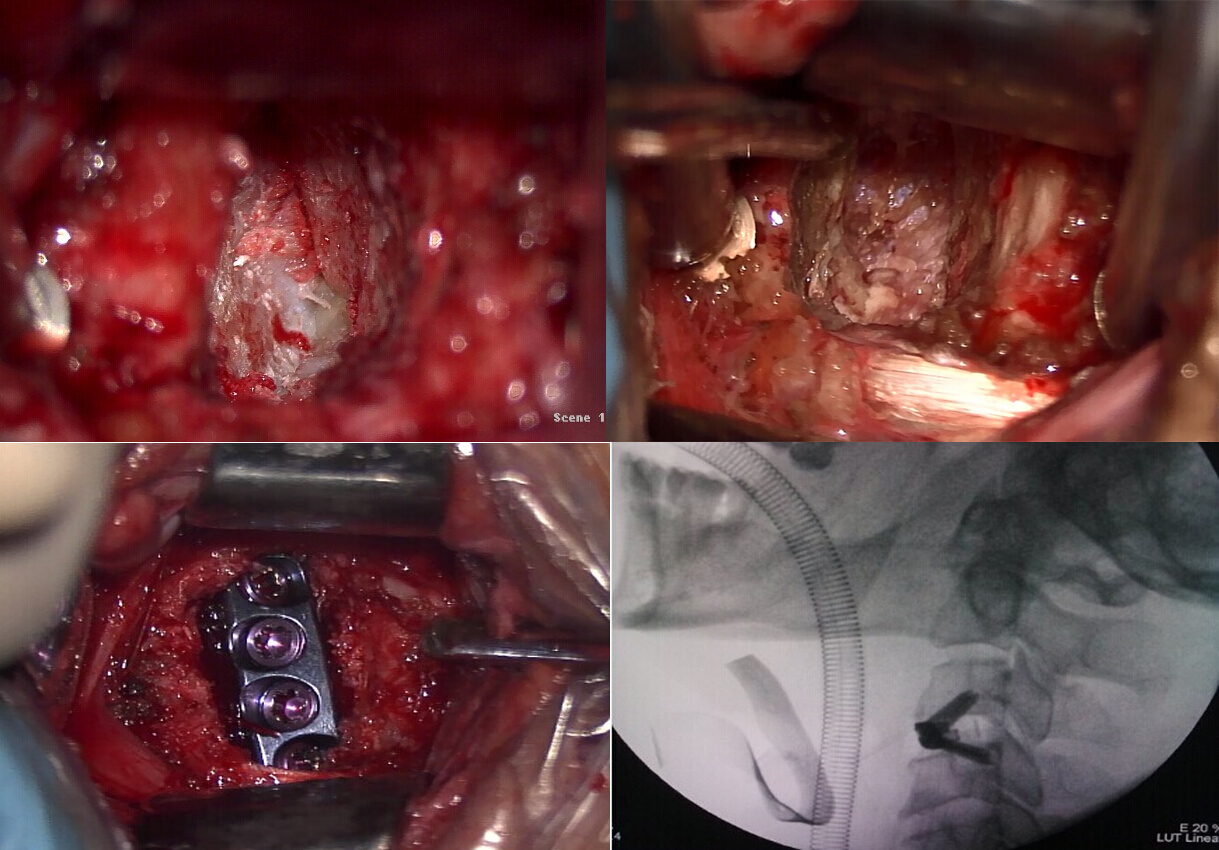

完善各项术前检查及准备后,神经外科江玉泉主任、王磊和姜政副主任医师及韩利章医师于2014年12月23日为患者实施手术。术中于显微镜下行颈3-4椎间盘髓核及纤维环切除,切除突入椎管内的髓核组织,并取磨钻磨除椎体后缘增生的骨质。切除后纵韧带,见硬膜囊膨隆明显,减压充分(图2)。并首次应用了强生公司的Zero-P零切迹椎间融合器行颈椎间融合术。术后患者四肢麻木及无力症状较术前明显改善,并主诉无明显吞咽困难或吞咽不适的症状。术后复查颈椎平片及CT示效果满意(图3)。

图2

图3